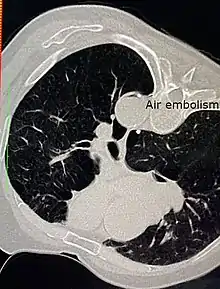

| Air embolism | |

An air embolism, also known as a gas embolism, is a blood vessel blockage caused by one or more bubbles of air or other gas in the circulatory system.[1] Air can be introduced into the circulation during surgical procedures, lung over-expansion injury, decompression, and a few other causes. In flora, air embolisms may also occur in the xylem of vascular plants, especially when suffering from water stress.[2]

When air enters the veins, it travels to the right side of the heart, and then to the lungs.[15] This can cause the vessels of the lung to constrict, raising the pressure in the right side of the heart. If the pressure rises high enough in a patient who is one of the 20% to 30% of the population with a patent foramen ovale, the gas bubble can then travel to the left side of the heart, and on to the brain or coronary arteries. Such bubbles are responsible for the most serious of gas embolic symptoms.

Venous or pulmonary air embolism occurs when air enters the systemic veins and is transported to the right side of the heart and from there into the pulmonary arteries, where it may lodge, blocking or reducing blood flow.[16] Gas in the venous circulation can cause cardiac problems by obstructing the pulmonary circulation or forming an air-lock which raises central venous pressure and reduces pulmonary and systemic arterial pressures.[16][17] Experiments on animals show that the amount of gas necessary for this to happen is quite variable.[10] Human case reports suggest that injecting more than 100 mL of air into the venous system at rates greater than 100 mL/s can be fatal.[18] Very large and symptomatic amounts of venous air emboli may also occur in rapid decompression in severe diving or decompression accidents, where they may interfere with circulation in the lungs and result in respiratory distress and hypoxia.[8]